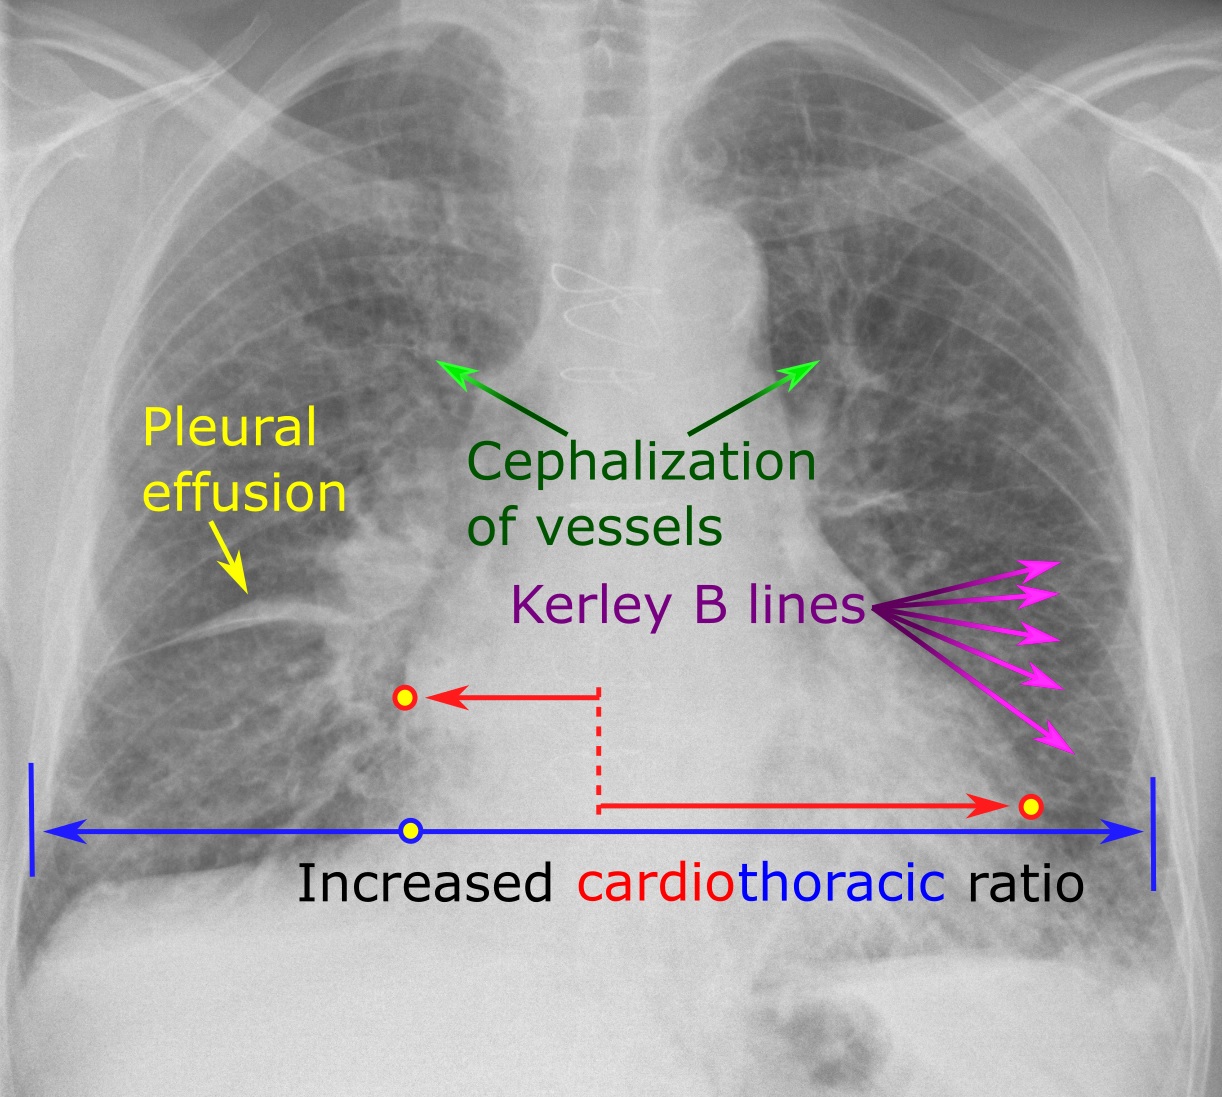

- Chest X-ray – can be used to image any problems or abnormality in lung pathology (e.g. pleural effusions etc).

- Pleural effusion